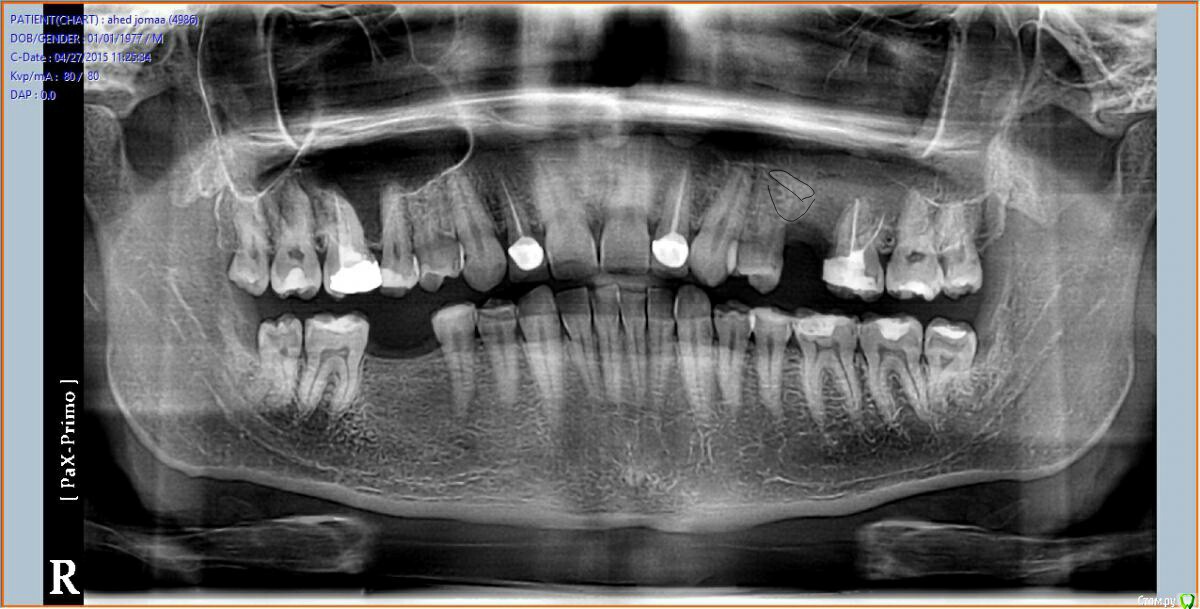

bilal Опубликовано 27 апреля, 2015 Поделиться Опубликовано 27 апреля, 2015 (изменено) добрый вечер.обратился пациент от другого врача. со слов пациента месяц назад удалил 25, обратился с жалобами на гноетечение из носа слева и сообщение с пазухой на месте удаления, по снимку видно что там корень от 25 остался в пазухе.вопрос: каким путем лучше достать через лунку и сообщение с пазухой или латерально как при открытом синус лифте, и сообщение лучшее закрыт сразу или оставить для промывание на пару дней.кт нет возможности делать .спасибо заранее Изменено 27 апреля, 2015 пользователем bilal Ссылка на комментарий

Kev Опубликовано 28 апреля, 2015 Поделиться Опубликовано 28 апреля, 2015 Ребята, что-то с телефона не могу рассмотреть где там корень в пахузе на ОПТГ, покажите. Ссылка на комментарий

bilal Опубликовано 28 апреля, 2015 Автор Поделиться Опубликовано 28 апреля, 2015 Вот, нарисовал границы пазухи и корень, как я вижу Ссылка на комментарий

Большой Зеленый Опубликовано 29 апреля, 2015 Поделиться Опубликовано 29 апреля, 2015 Что то не похоже на корень. 5 Ссылка на комментарий

Strelok96 Опубликовано 29 апреля, 2015 Поделиться Опубликовано 29 апреля, 2015 Тоже не вижу корень на снимке, надо делать КТ. 2 Ссылка на комментарий

alekszander Опубликовано 29 апреля, 2015 Поделиться Опубликовано 29 апреля, 2015 не стал бы я лезть без более тщательной R-диагностики, и скорее всего бы все же направил бы на эндоскоп.PS про корень который не видят, как-то постеснялся спросить, поскольку сколько не смотрю так и не вижу его. 1 Ссылка на комментарий

kriokov Опубликовано 30 апреля, 2015 Поделиться Опубликовано 30 апреля, 2015 Вот, нарисовал границы пазухи и корень, как я вижусделайте обычный прицельный снимок, если корень так низко как вы отметили-- будет видно. 2 2 Ссылка на комментарий